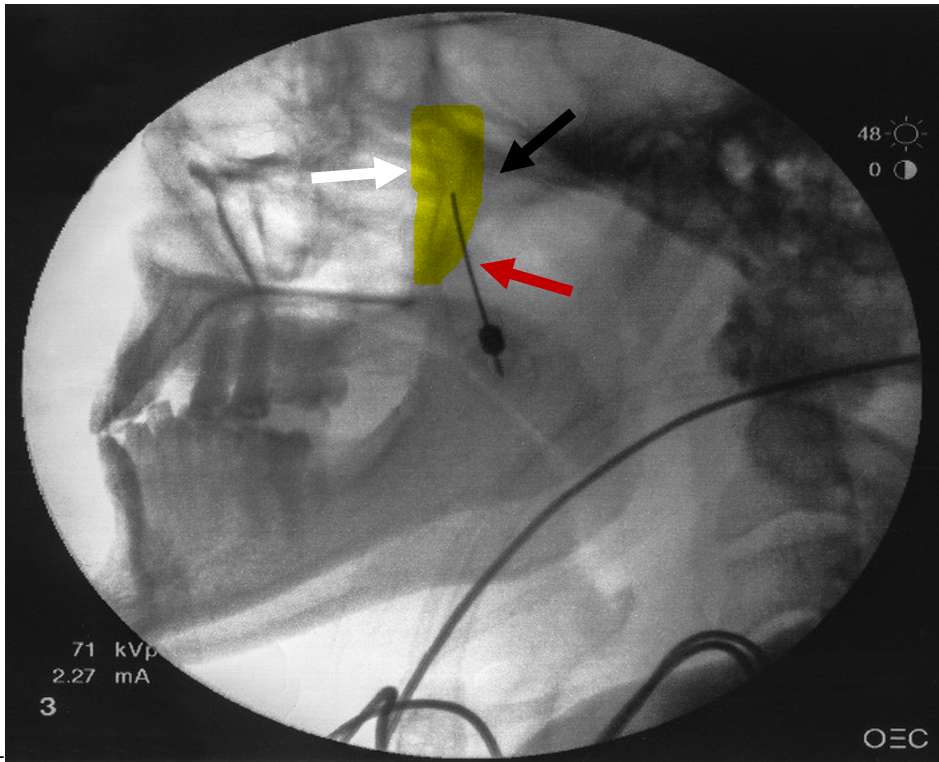

Figure 1: Lateral fluoroscopic view

White arrow indicates the pterygopalatine fossa that is highlighted in yellow. Black arrow represents the pterygopalatine plate located posterior to the fossa. Red arrow represents the needle with tip being advance superiorly and medially into the pterygopalatine fossa

- A 22- or 25-gauge, 3½-inch spinal needle with a slightly bent tip is inserted coaxially with lateral fluoroscopic guidance. This view is the main view used while advancing the needle toward the pterygopalatine fossa. The needle is advanced superiorly and medially toward the pterygopalatine fossa (Figure1).